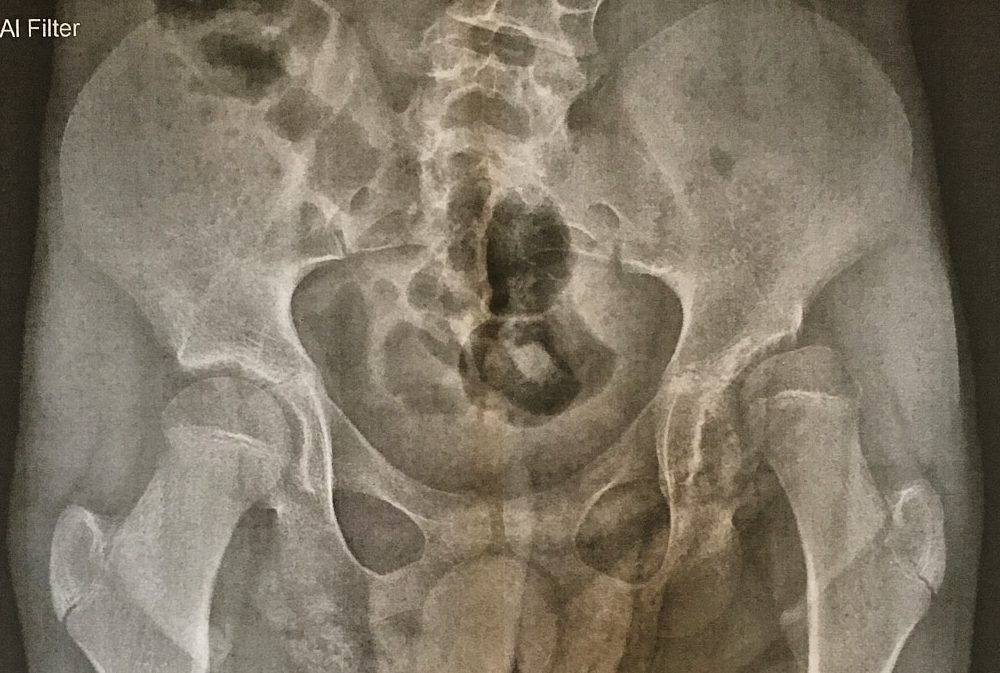

Beim Orthopädentermin im Juni hat es sich ja schon angedeutet, jetzt haben wir die Bestätigung durch die Klinik. Fabian wird 2018 eine ähnliche Hüftoperation brauchen, wie Jana letztes Jahr. Der Hüftkopf steht schon zu über 50% außerhalb der Hüftpfanne, was zum einen Schmerzen bereiten könnte und zum anderen in absehbarer Zeit seine Bewegung stark einschränkt. Die Operation weiter nach hinten zu verschieben, macht keinen Sinn, da bei Fabian die Wachstumsfugen in der Hüfte noch nicht verschlossen sind und somit die Voraussetzungen für die OP deutlich einfacher sind. Wir haben Fabian deshalb heute in der Klinik „Dritter Orden“ in München vorgestellt und mit Herr Dr. Frimmberger eine mögliche OP besprochen. Das Hauptproblem aus unserer Sicht ist die Ruhigstellung über 6 Wochen in einem Becken-Bein-Gips. Hier gibt es aber eventuell eine Möglichkeit durch die Sonderanfertigung einer speziellen Hüftorthese die Bewegung bei Fabian nicht zu 100% einzuschränken. Außerdem muss nicht zwingend an den Klinikaufenthalt eine Reha anschließen, sofern eine entsprechende Versorgung und Therapie zuhause gewährleistet ist. Wir sind jetzt so verblieben, dass ein Operationstermin für März/April 2018 geplant wird. Details zum Ablauf und zur OP-Technik werden klinikintern noch diskutiert. Auf jeden Fall wird 2018 auch wieder ein anstrengendes Jahr werden.